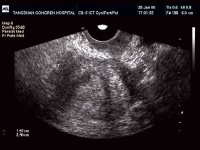

B超检查[编辑 | 编辑源代码]

子宫超声检查对子宫内膜癌在宫腔大小、位置、肌层浸润程度、肿瘤是否穿破子宫浆膜或是否累及宫颈管等有一定意义,其诊断符合率达79.3~81.82%。有报道,对45岁以上病人检查,并与宫腔镜检及活检对照,超声的准确率约为87%。另外,谢阳桂等行B超检查参照UICC分期方法,根据肿瘤部位、肌浸、宫旁及邻近器官受累情况,与手术探查和病理对照,其分期符合率达92.9%。B超为检查对患者无创作性及放射性损害,故它是子宫内膜癌的常规检查之一。尤其在了解肌层浸润及临床分期方面,有一定参考价值。